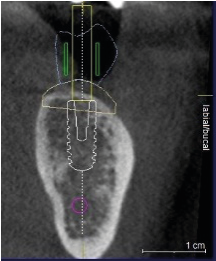

se realiza planeación quirúrgica computarizada, confección de guía de fresado y de provisionales acrílicos.

Zona postero superior derecha para aprovechamiento del hueso disponible y evitar elevacion de seno maxilar.